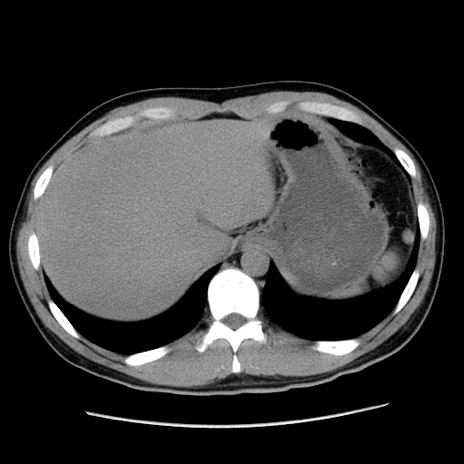

症例36(横断像)

【症例】20歳代 男性

【主訴】心窩部痛

【現病歴】今朝より上腹部痛あり。一旦軽快していたが再度出現したため救急要請。昨日夕に白身の魚を含む刺身を食べた。

【身体所見】BP 136/89mmHg、HR 74/min、BT 37.0℃、腹部:膨満、軟、心窩部に圧痛あり。反跳痛なし、筋性防御なし、腸雑音やや亢進あり。

【データ】WBC 17700、CRP 0.48